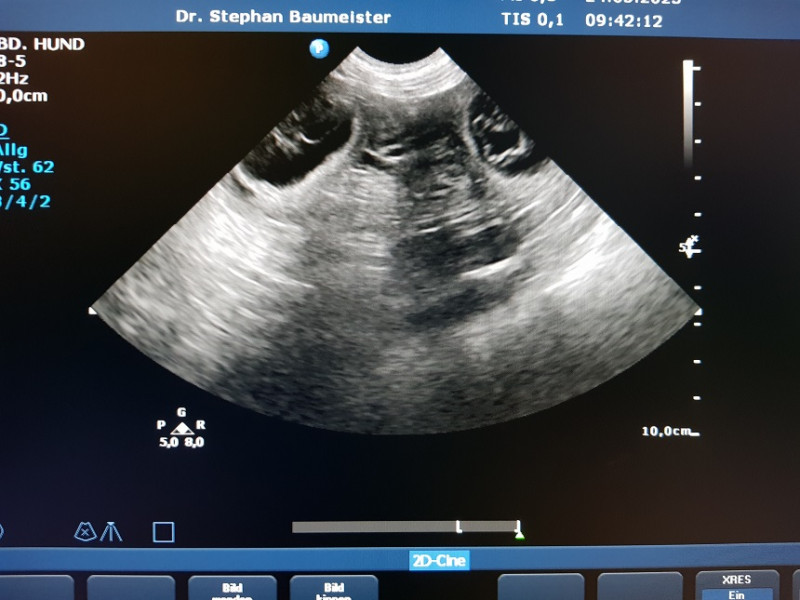

21. u. 23. April Deckmeldung

Am Freitag den 21. ging es zum 1. Progesterontest zu unserem Tierarzt....für mich war es der 9. Tag der Läufigkeit. Mein Mann war gerade wieder mit Yule zu Hause, rief unser Doc an...ihr könnt zum Decken, Yule ist schon soweit. Wie gut daß der Deckrüde diesmal in der Nähe stand....weiterlesen demnächst im Wurftagebuch